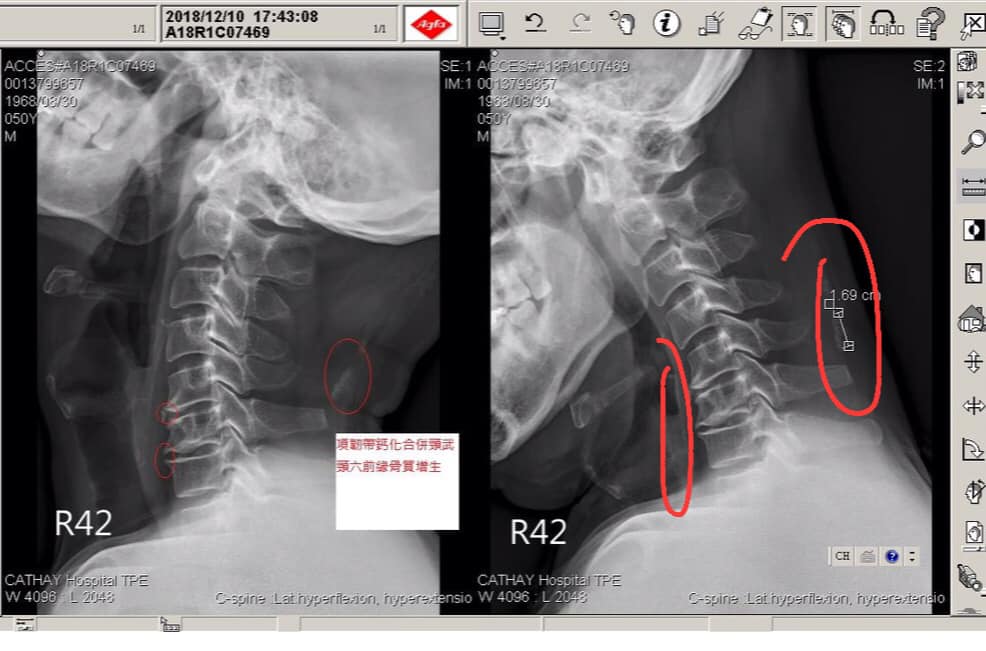

盧先生,年過剛好半百,從去年十一月開始左頸疼痛,一開始只是頸椎痠痛,結果很快的手肘伴隨大拇指跟食指與中指麻痛,他回想當初只是換燈泡不小心跌倒,撞擊到肩部跟頸椎,事發後第二天就開始痛,原本想說吃止痛藥休息就好,結果情況一直惡化,最後痛到手肘來,一直在刺痛,幾乎到晚上沒辦法睡覺,晚上靠著兩顆止痛藥跟兩顆安眠藥才能小睡一兩個小時,去看骨科拍過x光說頸椎過直,第五第六椎體變扁合併前緣骨質增生(如圖),症狀一直沒改善,大醫院又安排核磁共振,証實第五第六兩個椎間盤同時突出壓迫(如圖),這中間拉脖子也拉了幾次效果仍不好,每天只能靠止痛藥跟安眠藥,但是一個晚上還是會醒來好幾次,就是手肘一直在刺痛,神外醫師建議如果還是非常痛,可能要安排動刀。